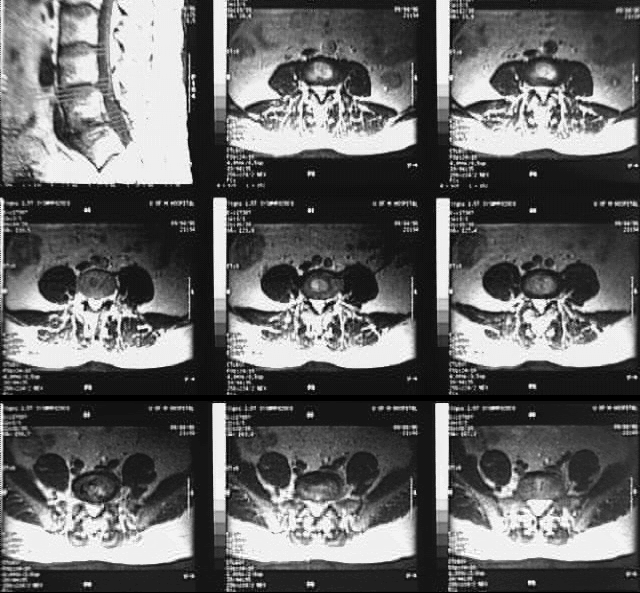

Radiology Images

Back- Lumbar Spine MRI Cross